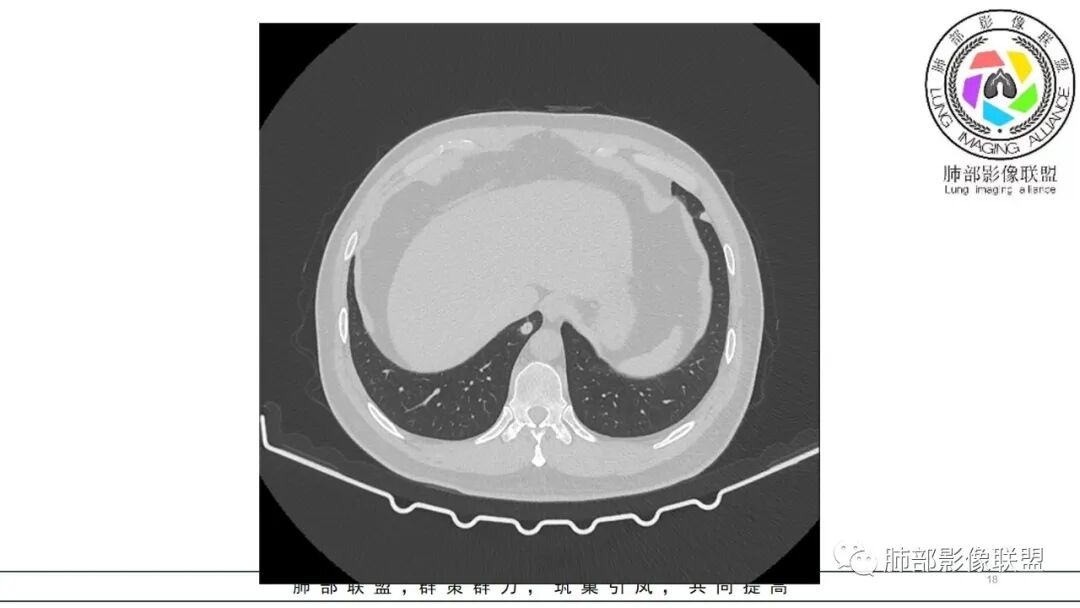

中年男性,咳嗽咳痰低热三天。右肺中叶、下叶条片状高密度影,局部边缘有晕,可见卫星灶。双肺另见多发小结节。考虑炎性肉芽肿,PC,鉴别GPA

中年男性,咳嗽咳痰伴发热3天,有鼻窦炎、 中耳炎病史,血沉、 CRP 增高,中性粒稍高。

双肺多发实性小结节,边清,多位于胸膜下。右肺中叶不规则实变影,沿支气管血管束走行,似有跨叶。

中年男性,咳嗽咳痰发热,鼻炎中耳炎,血沉高,右肺中叶条状高密度实变影,边界清楚 ,双肺散在小结节,部分小空洞,首先考虑GPA,鉴别结核

双肺胸膜下多发结节,部分结节内可见空洞影。右肺中叶斑片影(类似指套征),并可见右肺中叶支气管壁增厚。看到病史的时候,看到鼻窦炎,中耳炎。想到如果与鼻窦炎相关,1.有GPA,但是GPA,典型是鼻,肺和肾的病变,有鼻窦炎,软骨受累,眼睛受累红肿等。晨读没有提到肾方面损害。另外,晨读的结节更多表现为血播,与支气管血管束关系不大。如果是GPA应该主要是与血管相关,与支气管血管束密切相关。2.和鼻窦炎有关的真菌感染,曲霉?但是肺内病变难以一元,右肺中叶与气道相关,双肺多发结节与血道相关。不是说一般气血难以兼容。还有就是如果是曲霉的指套,密度偏低了。3.按两肺多发结节方向考虑,隐球菌需要鉴别。总之,晨读隐球菌>GPA>真菌曲霉

男,47岁,咳嗽咳痰发热三天,既往中耳炎病史。CT示双肺多发随机分布小结节,多位于胸膜下,部分伴小空洞,右肺中页不规则实变影,沿支气管血管束走行。实验室检查血沉,CRP增高。综合考虑为感染性病变,隐球可能,鉴别GPA

双肺多发结节,以胸膜下分布为主,形态相似,边缘较规整,少部分边缘晕征,无分叶毛刺;右肺中下叶多结节融合并实变影,边缘平直、U形征,跨叶。

病灶与支气管血管束无关,定位肺实质来源病变,考虑良性病变,炎性肉芽肿病变:隐球可能。

中年男性,咳嗽咳痰低热3天,偶有血痰。有鼻炎、中耳炎病史。右中叶病灶呈指套样,跨右下叶,叶间胸膜牵拉移位。两肺胸膜下多发结节灶,边缘模糊见晕征,部分呈空洞结节。白细胞计数及CRP、血沉稍高。跨叶的指套样病灶有小细胞肺癌的影像特点,两肺多发结节,但近肺门、纵隔无肿大淋巴结,不符合小细胞肺癌的转移特点,考虑非肿瘤病灶。没有典型的多形态、未见树芽征,肺结核可能性小;两肺胸膜下病灶有晕征,存在隐球菌病可能,但右中下叶的主病灶形态在隐球菌病中罕见;有鼻炎病史,肺内病灶存在血管炎可能;患者为银行职员,应该经常接触纸币,有血痰症状,主病灶呈指套样,两肺多发晕征及空洞,存在曲霉菌感染可能。综上考虑肺曲霉菌病可能,鉴别血管炎、PC、TB。